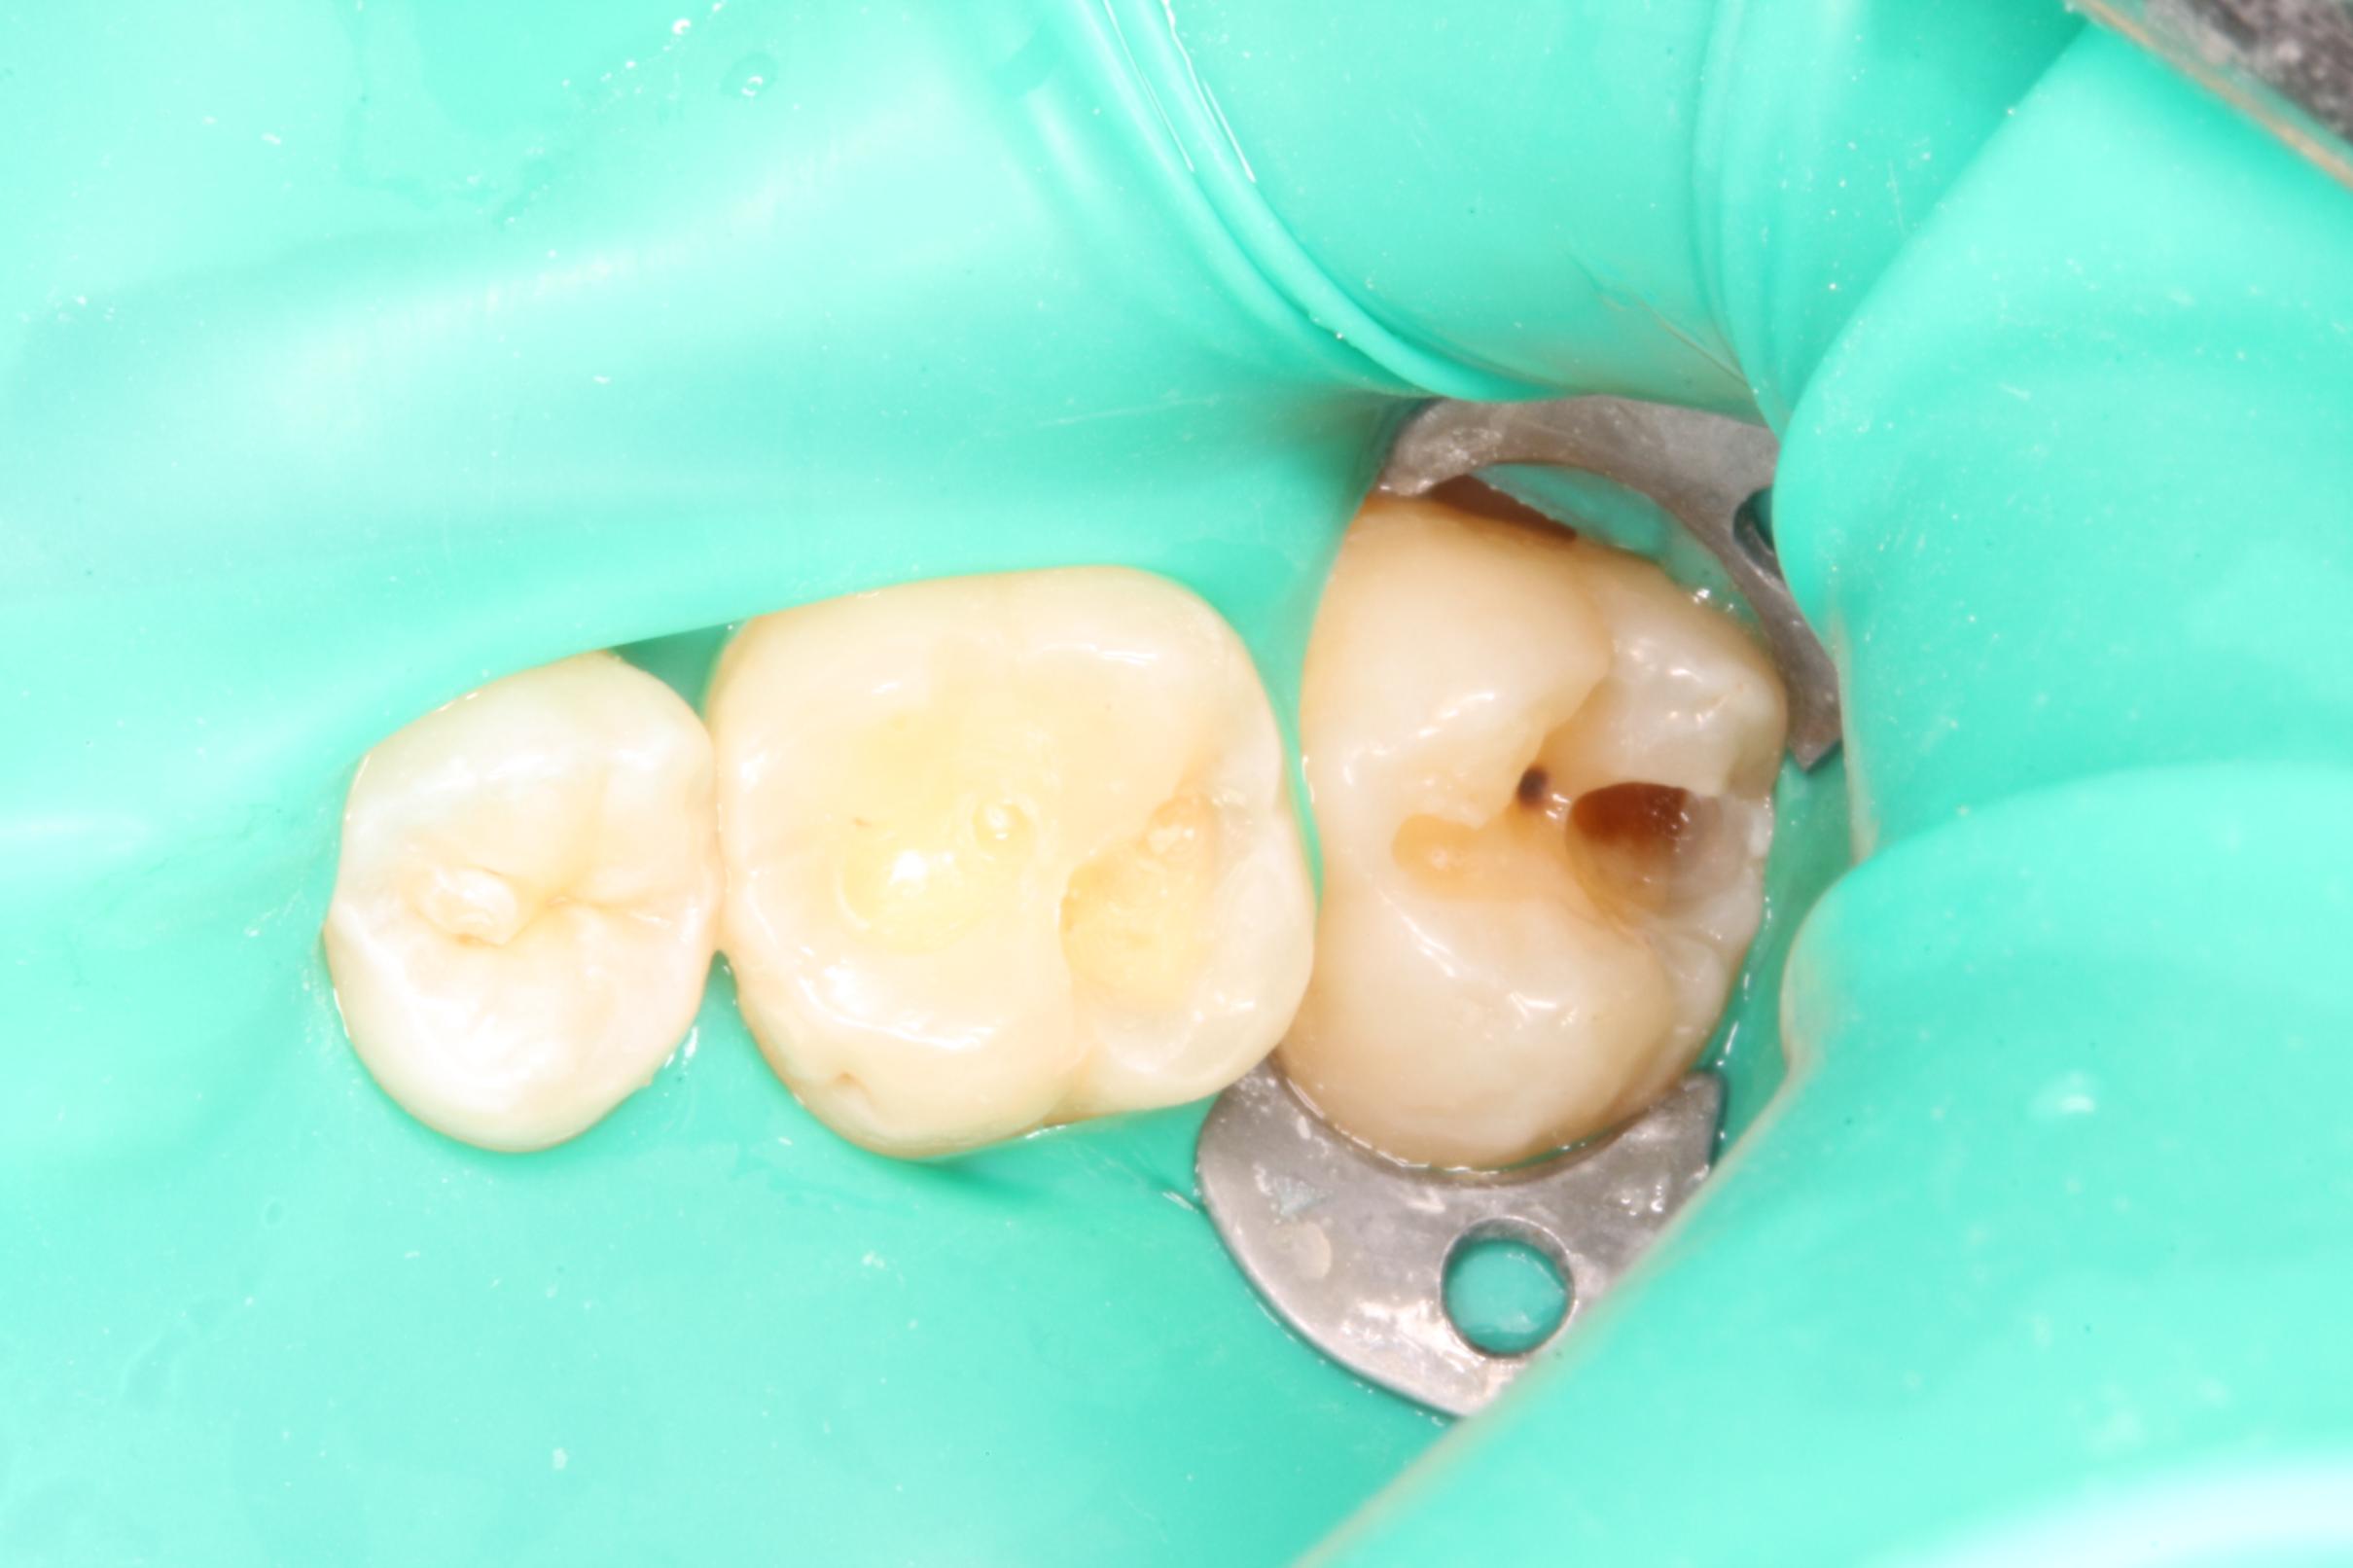

La goma dique es una lámina fina de látex que el odontólogo coloca alrededor del diente que va a tratar. Su función principal es aislar el diente del resto de la boca, manteniéndolo limpio, seco y libre de saliva o bacterias durante el procedimiento.

En pocas palabras, es como un “campo de trabajo estéril” que protege tanto al diente como al paciente.